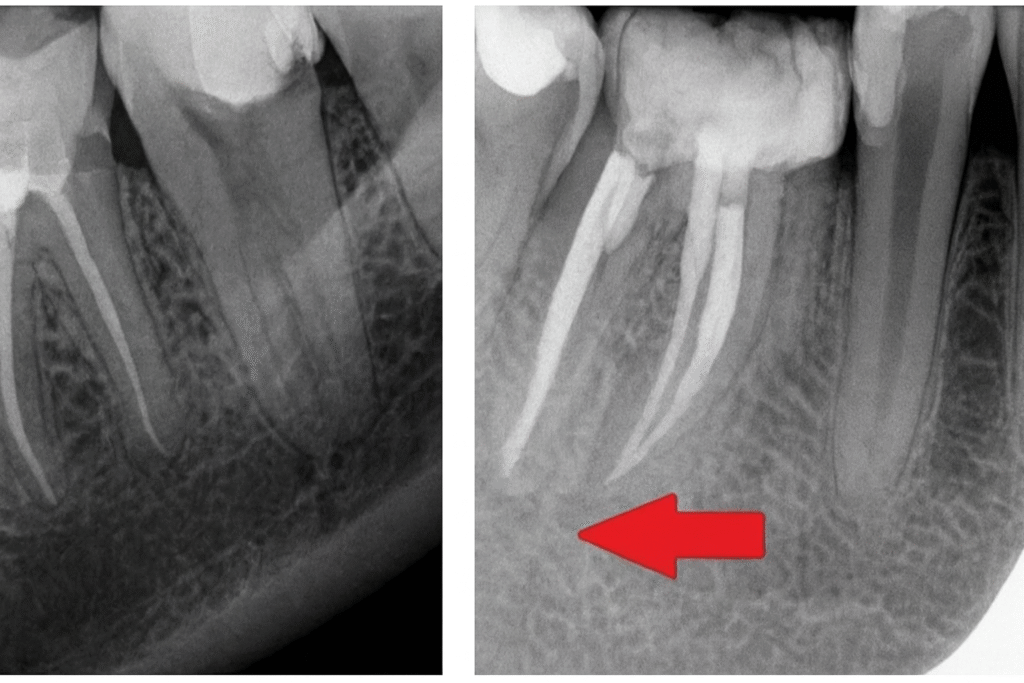

Radiowizjografia pozwala nam m.in. na:

- ocenę stanu tkanek okołowierzchołkowych zęba,

- analizę kształtu i przebiegu kanałów korzeniowych,

- wykrycie obecności pozostawionych korzeni zębów,

- weryfikację skuteczności i poprawności leczenia kanałowego.